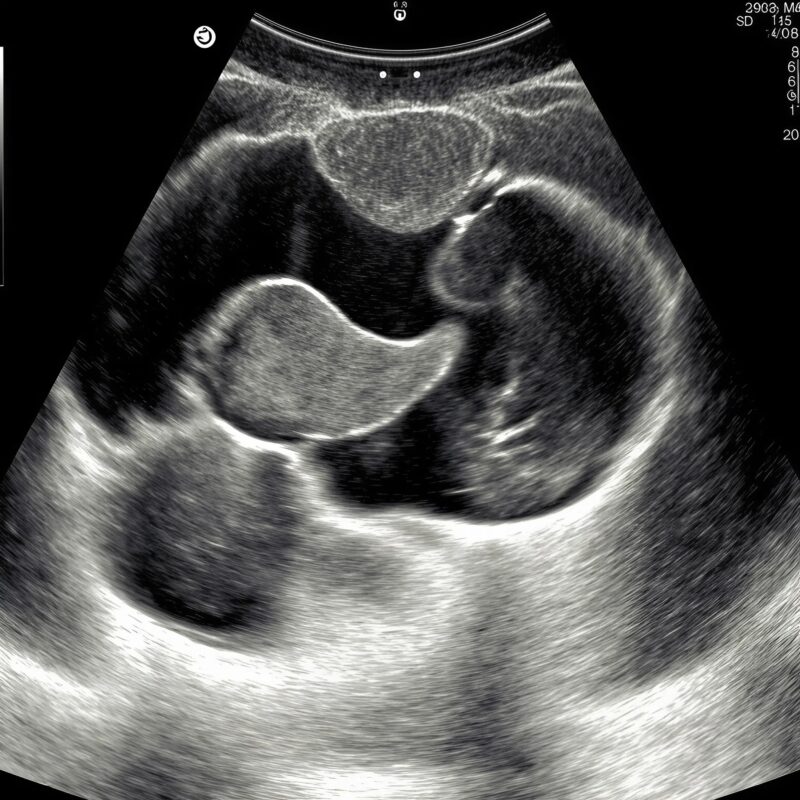

I looked at the screen again. Our child floated in black velvet, flexing the tiniest hand as if counting. One, two, three—then a curl of fingers against the chest, a gesture so tender it felt like an answer. I didn’t know to what, only that it answered me. ✨

At night, when the house went quiet, the ceiling turned into a projection of everything we’d seen. The dotted circle pulsed like a moon. David lay beside me, hands folded over mine. “He’s strong,” he whispered. “Look how he moves.” Our baby did move, a slow tumble, then a small kick that sent a ripple across my stomach. The movement felt like a promise—I didn’t know what kind, only that it had the weight of truth. We chose a name we kept secret between us, the shape of it like a pebble in the pocket, warm from touch.

Week twenty-two. The images grew sharper; the baby grew angles. The placental lake looked like a halo. The spine brightened like a road at dawn. And always, the pause—a short break in the line. The surgeon met us in a room with a frosted window, hands warm, eyes straightforward. “If there’s an open lesion, we’ll protect the area at birth and plan early repair,” she said. “We’re better at this every year.” She smiled, not the smile that says don’t worry, but the one that says I’ll be there when you do. I carried that smile home like a lantern. 🕯️

He cried the moment air touched him. The sound was fierce, not a plea but an announcement. I cried too, from somewhere old and wordless. I saw only his face, wrapped and luminous, the nose that looked like David’s, the tiny lips already learning vowels. “Protect the spine,” someone said, and a team gathered in choreography, soft and precise. They covered the lower back with a sterile dressing and moved as if carrying light.

In the last scan—one more machine, one more monitor—the gap looked different. The sonographer frowning, then adjusting, then frowning again. “I need to try one thing,” she murmured. She repositioned our son on his side, lifted his tiny leg with astonishing gentleness, and angled the probe along a narrow corridor of sound. The image sharpened. The beads of the spine lined up, one after the other, unbroken. Where the darkness had opened before, light threaded through like a needle. The room stayed silent long enough for me to believe it, and then the sonographer laughed, a soft breath of disbelief.